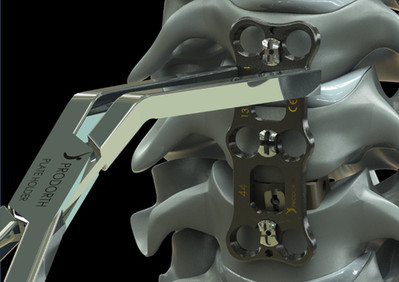

Anterior Cervical Plate System

El sistema de placas cervicales Prodorth está diseñado para satisfacer las expectativas clínicas de la cirugía cervical anterior y ofrece una amplia gama de tamaños de placas y tornillos.

- Placas predobladas de bajo perfil (2,0 mm).

- Destornillador único para colocar tornillos y asegurar el mecanismo de bloqueo.

- Los diferentes tornillos óseos se pueden identificar por su codificación de color única.

- Alto grado de angulaciones de tornillo.

- Mecanismo de bloqueo simplificado de los tornillos.

- Tornillos autorroscantes.

- Roscas de tornillo profundas para una alta resistencia a la extracción.

- Amplios espacios de injerto.

- El sistema de placa cervical de Prodorth consta de placas cervicales, casquillos de cierre, tornillos óseos y los instrumentos necesarios para implantar este sistema específico. Todos los componentes del implante están hechos de una aleación de titanio Ti6Al4V-ELI (Grado 23) (ASTM F136 / ISO 5832-3).